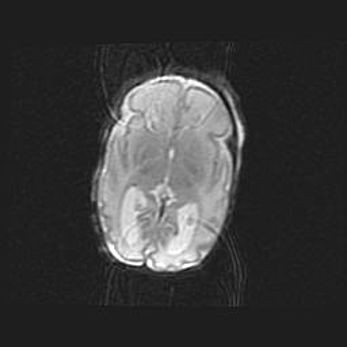

Лейкомаляция с кистозно-глиозной дегенерацией головного мозга.

Возраст: 2 месяца 25 дней

Вес: 6400 г

Окружность головы: 40 см

Срок гестации: 41 неделя

Лейкомаляцию относят к ишемически-гипоксическим повреждениям головного мозга, диагностируемым у новорожденных. При лейкомаляции в головном мозге обнаруживают очаги некроза, возникшие после тяжелой гипоксии и нарушения кровотока. В процессе морфогенеза очаги проходят три стадии: 1) развития некроза, 2) резорбции и 3) формирования глиозного рубца или кисты. Перивентрикулярная лейкомаляция (ПЛ) встречается примерно в 12% случаев среди новорожденных, обычно – у недоношенных детей, причем, частота ее зависит от массы, с которой младенец появился на свет. Наибольшее число малышей страдает лейкомаляцией, если масса при рождении 1500-2500 г.